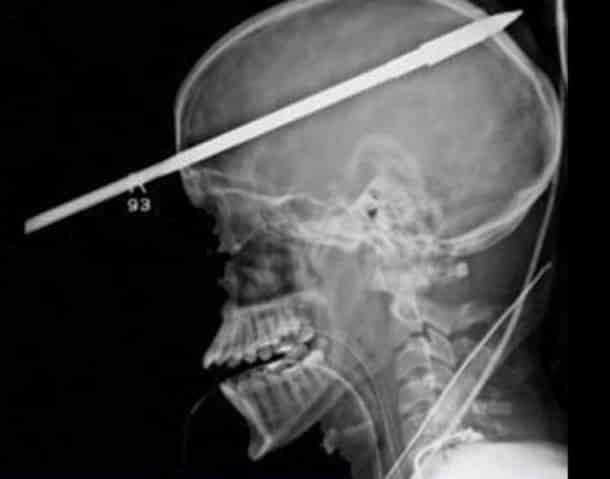

33 radiographies qui prouvent que les gens font des choses douteuses avec leur corps !